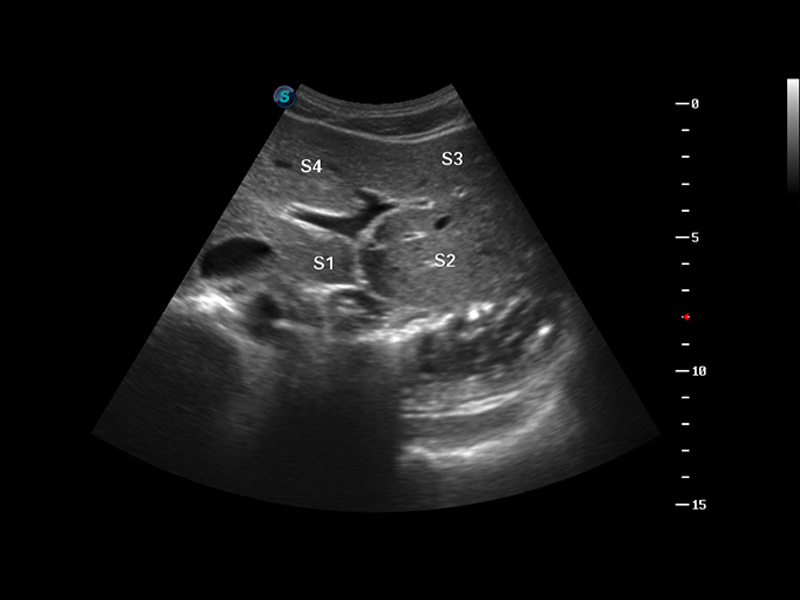

S8 EXP便携式彩色多普勒超声诊断仪是DB中国旗舰官方网站研发的高端全身应用型便携彩超。高通道的VIS平台融合可视化(Visual)、智能化(Intelligent)和人性化(Smart)的特点,配以DB中国旗舰官方网站自主研发生产的探头大家族,使您能够快速、准确的获得病人信息,提高工作效率的同时减轻疲劳。

成像技术

μ-Scan微米成像

谐波成像

空间复合成像